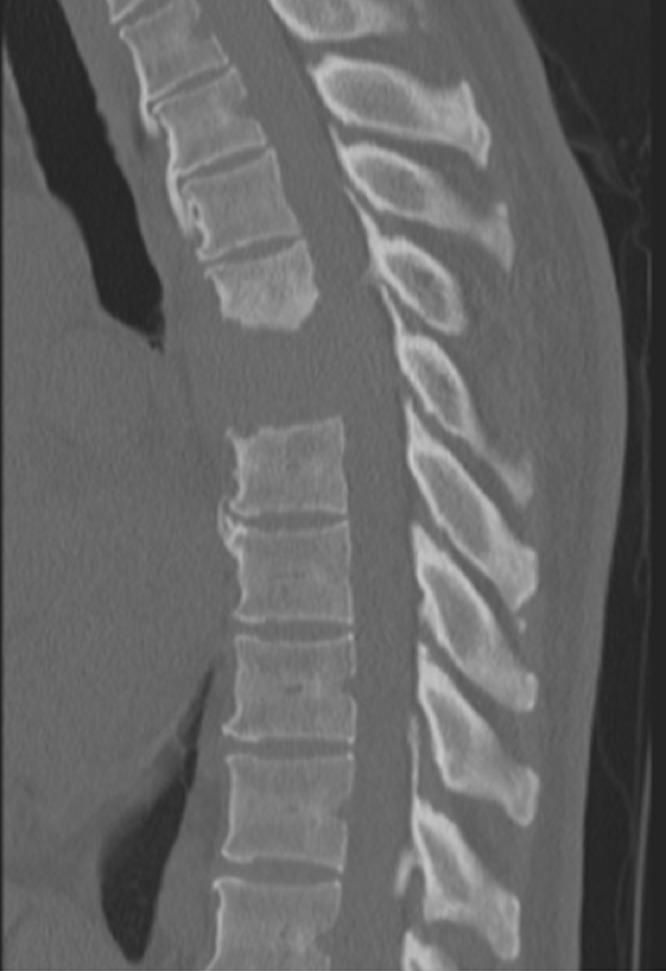

Thoracic Spinal Cord Compression Secondary to Metastatic Papillary Thyroid Carcinoma: An Unusual Oncological Phenomenon.

Cureus. 2022 Apr 17;14(4):e24206. doi: 10.7759/cureus.24206. eCollection 2022 Apr.

Unusual metastasis of papillary thyroid carcinoma to the spine: A case report.

Radiol Case Rep. 2023 Sep 7;18(11):4110-4114. doi: 10.1016/j.radcr.2023.08.078. eCollection 2023 Nov.